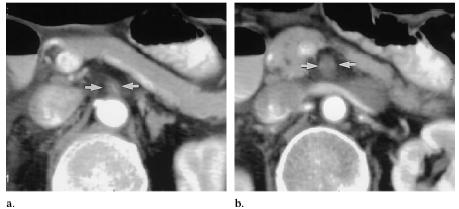

An intraoperative US image of the SMA showed the vessel and demonstrated flow within the vessel lumen. The SMA was patent, but the lumen was markedly narrowed and was no more than 1.7 mm in diameter (Fig 1). The SMA was nearly occluded at the division of the SMA into its branches at US. A thick circumferential hypoechoic wall or “halo” was seen. The hypoechoic wall thickening was diffuse and symmetric. There was no displacement of the vessel because of a mass. No focal aneurysms were identified in the proximal portion of the vessel. At spectral Doppler US (Fig 1c), turbulent flow was demonstrated. Computed tomography (CT) was performed after a bypass graft of the iliac artery to the SMA was successfully placed. On the CT scan, the proximal SMA wall was concentrically thickened (Fig 2a). There was distal focal occlusion of the SMA (Fig 2b). The bypass graft of the iliac artery to the SMA entered the SMA several centimeters distal to this occlusion.

Figure 2. (a,b) Selected transverse images obtained at contrast material–enhanced helical CT

demonstrate concentric thickening (arrows) of the SMA seen on a, with occlusion (arrows)

observed on b, a more caudal image.